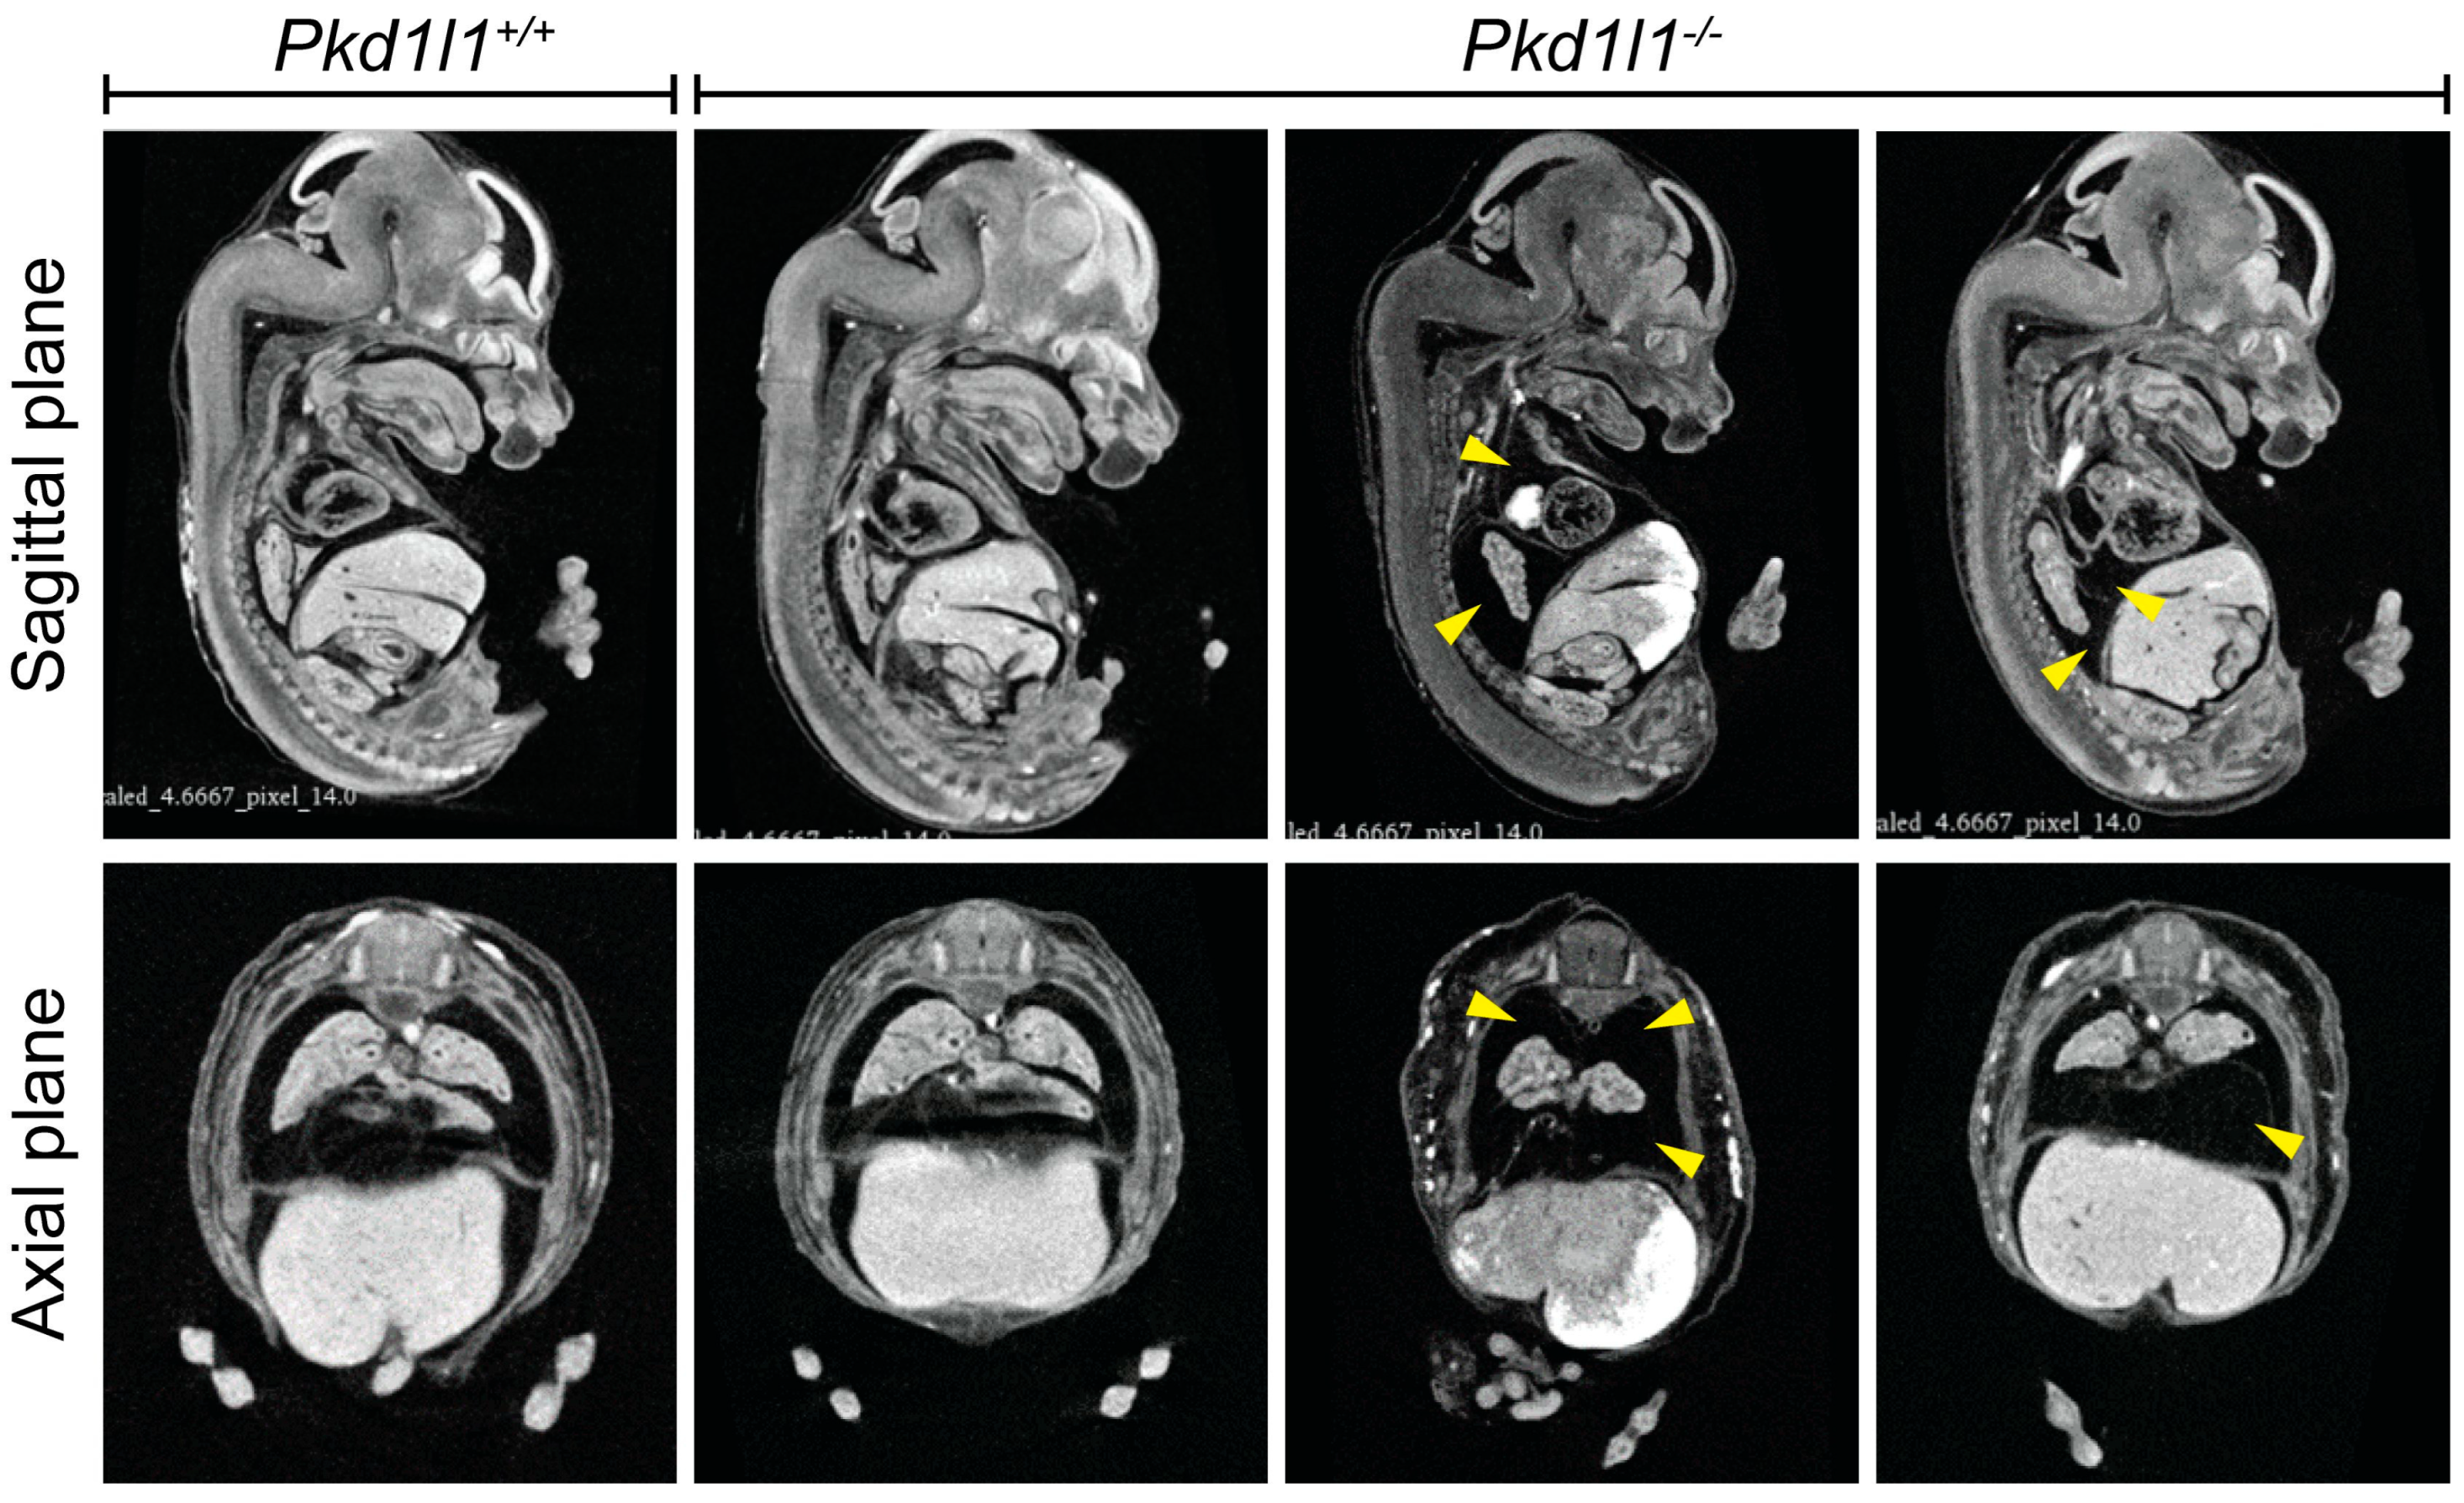

3.7. Observation of Pleural Effusion in Pkd1l1−/− Embryos